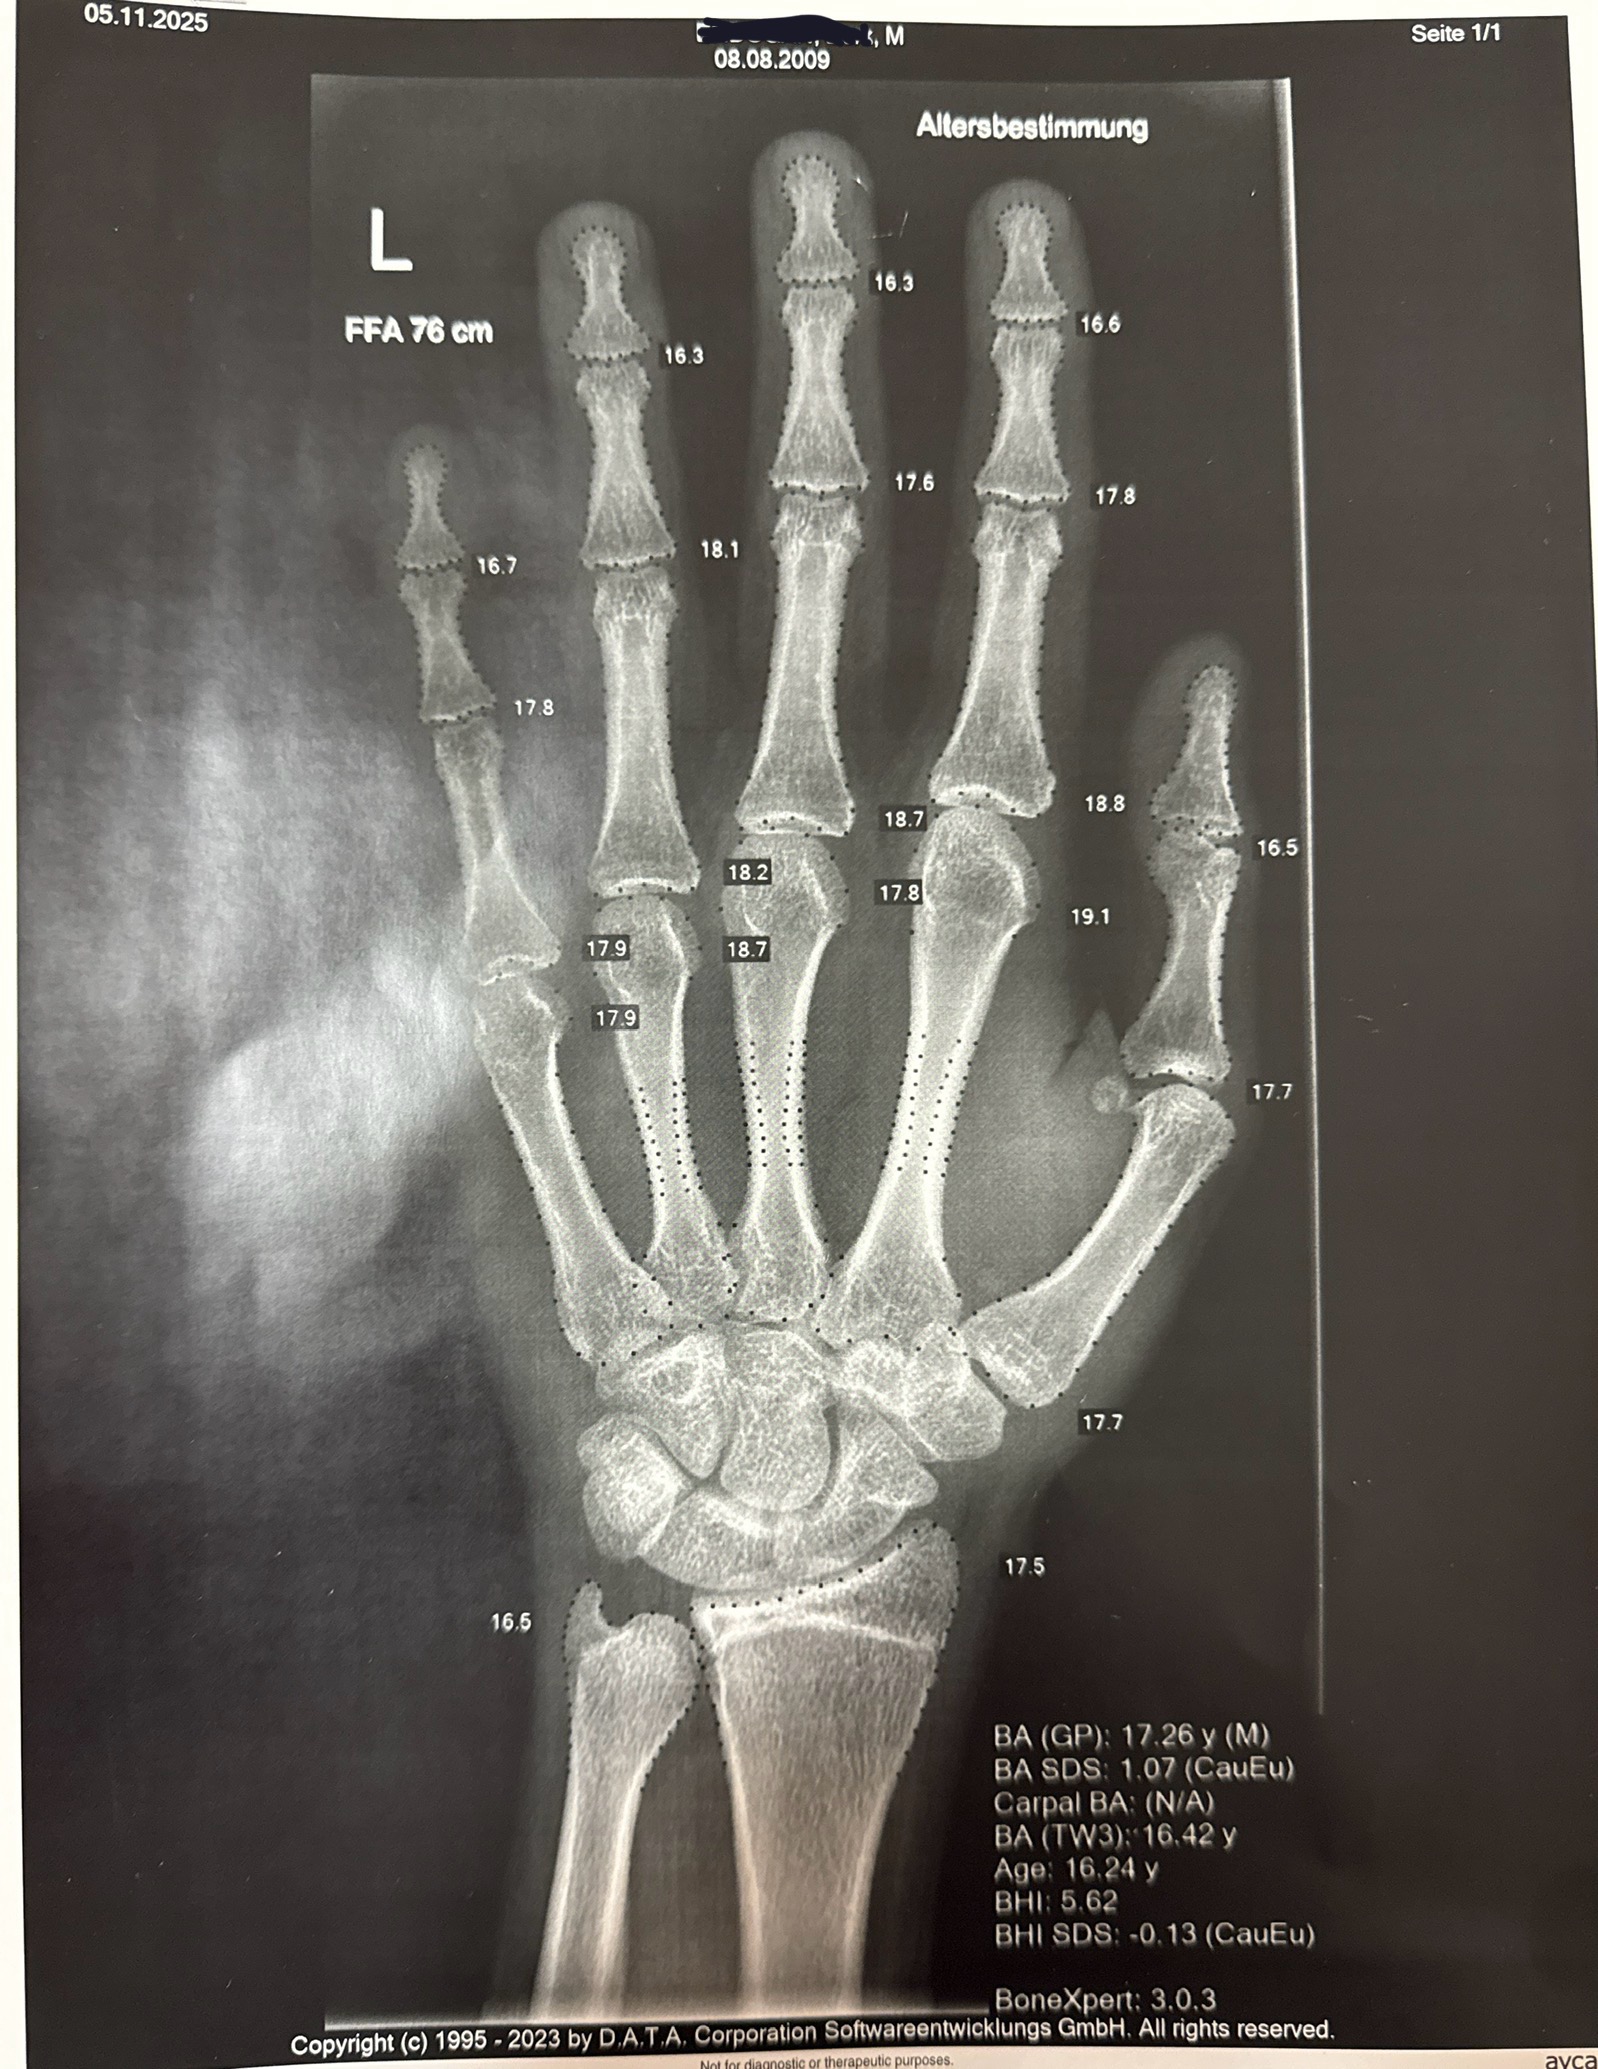

Proof im basically done developing: bone age is 17

bone age is written as BA which you can see

Includes: my name which I've censored. And my age in case somebody doesn’t believe im 16